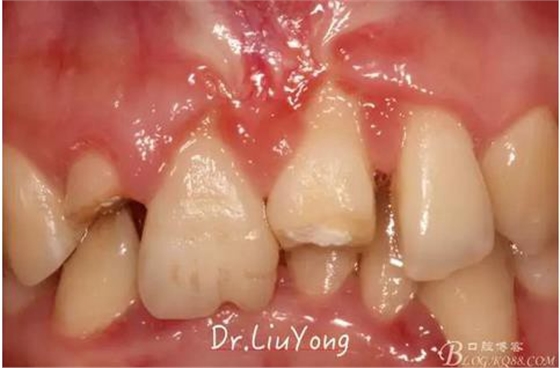

松動牙固定一月后拆除,A1-B2無明顯動度,但牙齦紅腫加重,給予全口齦上下潔治刮治術,上藥,醫(yī)囑加強口腔衛(wèi)生,氯己定漱口液含漱。

術后兩周復查,牙齦紅腫明顯好轉,探診不出血,但是此時A1唇側牙齦角形退縮1.5mm,B1唇側牙齦退縮3.5mm,B1遠中牙齦乳頭萎縮明顯,B2近中牙齦萎縮約1mm,且A1B1B2牙齦退縮處角化牙齦幾乎缺失,同時上唇系帶直接牽拉于B1齦緣。患者為高笑線女性,露齦笑,由于存在前牙區(qū)牙齦的高度嚴重不對稱及前牙牙冠過長的問題,因此嘗試通過膜齦手術改善患牙牙齦退縮。通過術前分析,A1唇側牙齦退縮屬于Miller分類第一類, B1唇側牙齦退縮屬于Miller分類第3類(B1遠中牙齦乳頭為2類,Nordland and Tarnow分類法),B2唇側牙齦退縮屬于Miller分類第3類,由于擬采用冠向復位瓣的方式治療牙齦退縮,因此需要先行上唇系帶修整術,解除上唇系帶帶來的過大牽引力。

潔治刮治后2周,如上圖